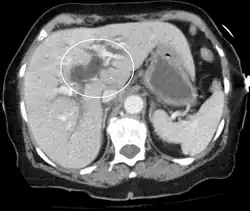

Dilatation des voies biliaires due à une obstruction (scanner, en section horizontale).

Dilatation des voies biliaires due à une obstruction (scanner, en section transversale).